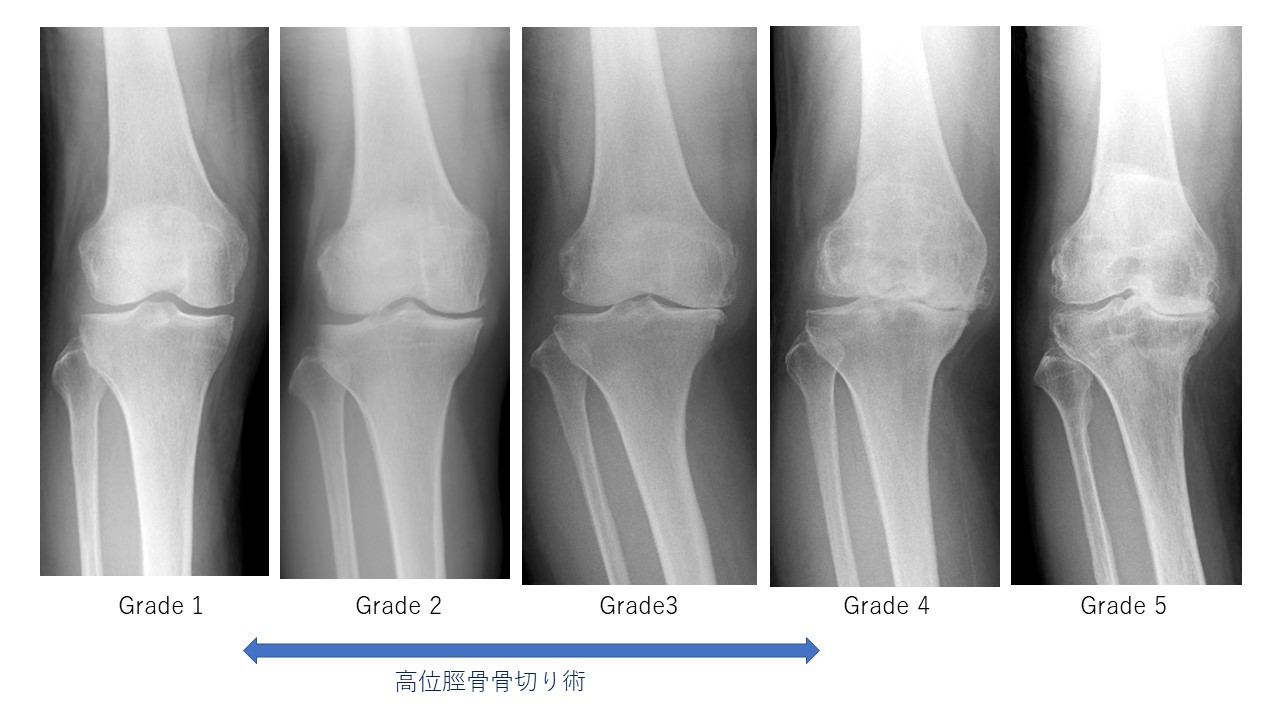

変形性膝関節症の分類とリハビリテーションプロトコール読みたい記事を探しませんか?